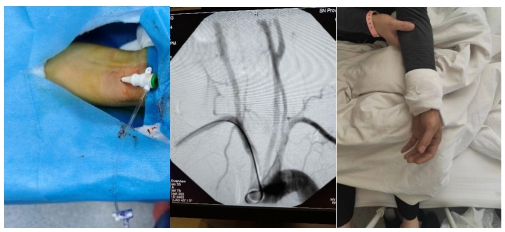

3月5日,陕西省中医医院脑病医院神经外科在介入手术室的密切配合下,成功实施首例经桡动脉穿刺脑血管造影术,填补了我院在这一技术领域的空白,标志着我院神经介入手术技术再上新台阶。

40岁的孙先生因枕部头痛伴视物重影6天入住脑病二科,头颅CT检查提示枕大池及左侧顶叶脑沟内高密度影,考虑蛛网膜下腔出血可能。住院后予以对症处理。为进一步明确颅内出血原因,脑病二科与神经外科介入团队详细讨论后,决定采用经桡动脉入路全脑血管造影术。手术非常顺利,用时仅50分钟,术后患者即可下地行走,自行如厕,无不良反应。

与传统的经股动脉穿刺造影术不同,经桡动脉造影术,是近些年发展起来,从手腕部进行穿刺置入导管鞘进行检查的脑血管造影术,相比于传统的经股动脉入路,经桡动脉入路有如下优点: